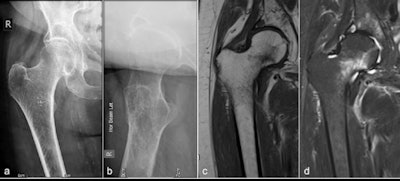

Plain x-ray versus MRI

The majority of femoral neck fractures are readily diagnosed on dedicated plain radiographs, but around 3% to 4% of hip fractures can be occult, resulting in a delayed diagnosis that can significantly increase morbidity and mortality, according to according to a literature search by Wong and colleagues (source: Scientific World Journal, 2013;2013:830319. World Journal of Emergency Surgery, 2015, vol. 10:1, pp. 55. Arch Orthop Trauma Surg., July 2010, Vol. 130:7, pp. 915-920).

The National Institute for Health and Care Excellence (NICE), an independent public body that provides guidance in England, recommends MRI in cases of suspected occult hip fracture within 24 hours, if dedicated radiographs are negative, they explained.